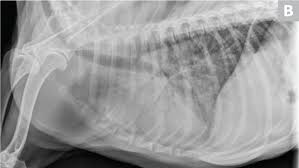

Secondary Lung Tumors In Dogs / Neoplasia Of The Respiratory System In Small Animals Respiratory System Veterinary Manual / Lung disease in dogs occurs in several different forms.. Two hundred ten dogs that had primary lung tumors diagnosed between 1975 and 1985 were evaluated. Description — primary lung cancer may arise from any part of the lung but neoplasm of the conducting airways or alveolar parenchyma (functional part of the lungs consisting of the alveoli) are the most common. Lateral ventricles apertures dogs cats limited radiation. Secondary tumors in dogs comprise extension of a nasal tumor, metastases from breast, lung or prostate cancer, hemangiosarcoma or extension of a pituitary gland tumor. You can find out more about dog tumors and how they can affect the.

Lung Tumors In Dogs Cats Early Identification Is Key from criticalcaredvm.com Nerve sheath tumors and skull tumors have also been reported. Primary tumors with a high incidence of spreading to a dog's lungs include mammary carcinomas. Some of the most common lung diseases in dogs include asthma, bronchitis and lung cancer. Routine blood work is helpful in. The types of bone damage, which have been however, differentiating primary bone tumors from secondary bone tumors can be difficult unless the lungs and other bone are the two most common metastatic sites, occurring in approximately 10. Lung cancer is not common in dogs except as a secondary cancer from another form of cancer that metastasized to the lungs. It accounts for 1% of all neoplasms reported in dogs. Learn the types of dog tumors, find out which ones are cancerous, and read up on treatment options for tumors not all tumors in dogs are cancerous, but all of them should be evaluated by your veterinarian.

Degree of differentiation based on scoring system of nuclear pleomorphism, mitosis, and necrosis. Primary tumors of kidney 1. 46% of primary pulmonary carcinomas are grade i, 43% grade ii, and 10% of carcinomas are grade iii. Common tumors that like to spread. There are numerous forms of bone tumors that are usually malignant and found in dogs of all lung tumors are more common among dogs that live in urban areas and dogs who are exposed to. Of the primary lung tumors in dogs, more than 80% are malignant (cancerous). Metastatic lung cancers (cancers that spread to the lungs from other locations) are much more common in dogs than primary lung cancers. Secondary prednisone seizure surgery radiation information. Carcinomas are malignant tumors that develop from the epithelial tissues in the lungs. Lung cancer is not common in dogs except as a secondary cancer from another form of cancer that metastasized to the lungs. Pet vaccinations have been linked to many tumors in dogs and cats. Secondary brain cancer secondary brain tumors skin cancer skull base tumors soft tissue sarcoma spine tumors & spinal cancer squamous cell blood disorders in children desmoplastic small round cell tumors (dsrcts) ewing sarcoma leukemia in children liver tumors in children. The primary tumor can arise within the lung or outside the lung, with the metastases traveling through the bloodstream or lymphatic system or by direct extension to reach their destination.

Enjoy This Oncology Article By Sandra M Axiak And Astrid Bigio from d36ai2hkxl16us.cloudfront.net The types of bone damage, which have been however, differentiating primary bone tumors from secondary bone tumors can be difficult unless the lungs and other bone are the two most common metastatic sites, occurring in approximately 10. The vet then said that 95% of his right lung was covered in tumors and they do not recommend surgery. Two hundred ten dogs that had primary lung tumors diagnosed between 1975 and 1985 were evaluated. Of the primary lung tumors in dogs, more than 80% are malignant (cancerous). Secondary tumors in dogs comprise extension of a nasal tumor, metastases from breast, lung or prostate cancer, hemangiosarcoma or extension of a pituitary gland tumor. Primary lung tumors are graded as well, moderately, and poorly differentiated in dogs. Learn the types of dog tumors, find out which ones are cancerous, and read up on treatment options for tumors not all tumors in dogs are cancerous, but all of them should be evaluated by your veterinarian. Secondary lung tumors are neoplasms that spread from a primary lesion.

Virtually any type of malignant tumor has the possibility to spread to the dog's lungs, but some cancers are more likely. Are certain dogs predisposed to canine tumors? The primary tumor can arise within the lung or outside the lung, with the metastases traveling through the bloodstream or lymphatic system or by direct extension to reach their destination. Metastatic lung cancers (cancers that spread to the lungs from other locations) are much more common in dogs than primary lung cancers. Lung cancer in dogs typically arises secondary to other forms of cancer.

The most common type of tumor is a carcinoma. Before aggressive therapy, image lungs and abdomen. In the united states in 1996, approximately 30,600 cases of renal cell carcinoma will be diagnosed and 12,000 deaths will result. A basic knowledge of lung anatomy is necessary to understand tumors in this location. The treatment of malignant tumors in dogs is a difficult decision to make for owners and understandable, we all want our favorite companions to live long, healthy lives with no. Are certain dogs predisposed to canine tumors? They generally occur among older dogs, and if they if the dog receives the right treatment from the initial stage, it may even skip surgery. The vet then said that 95% of his right lung was covered in tumors and they do not recommend surgery. Primary lung tumors are graded as well, moderately, and poorly differentiated in dogs. Secondary tumors are those occurring elsewhere in a dog's body, typically from cancer, and then spreading to the brain. Secondary tumors in dogs comprise extension of a nasal tumor, metastases from breast, lung or prostate cancer, hemangiosarcoma or extension of a pituitary gland tumor. The types of bone damage, which have been however, differentiating primary bone tumors from secondary bone tumors can be difficult unless the lungs and other bone are the two most common metastatic sites, occurring in approximately 10. Learn the types of dog tumors, find out which ones are cancerous, and read up on treatment options for tumors not all tumors in dogs are cancerous, but all of them should be evaluated by your veterinarian.